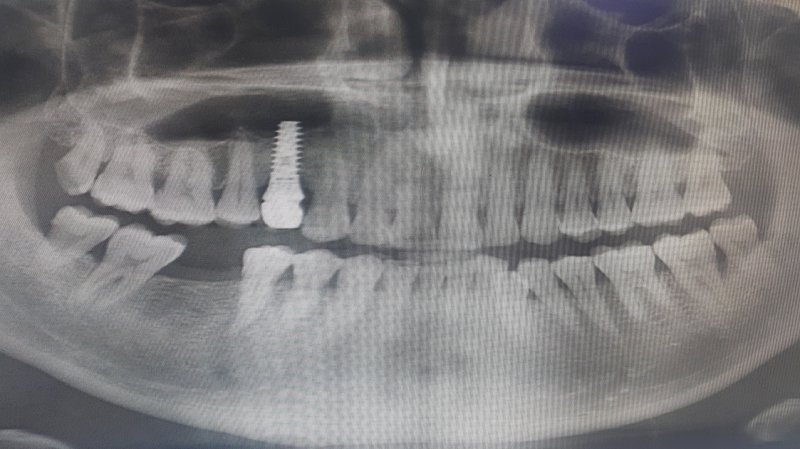

[서울=뉴시스] 28일 의사협회 의료광고심의위원회에 따르면 수년전 이미 '수면 임플란트'라는 표현이 환자에게 시술의 위험성을 간과하게 하고 치료 효과를 오인하게 할 우려가 크다고 판단해 해당 용어 사용을 불허했다. 해당 사진은 기사와 직접 관련이 없습니다. (사진=유토이미지 제공) 2026.01.28. photo@newsis.com *재판매 및 DB 금지